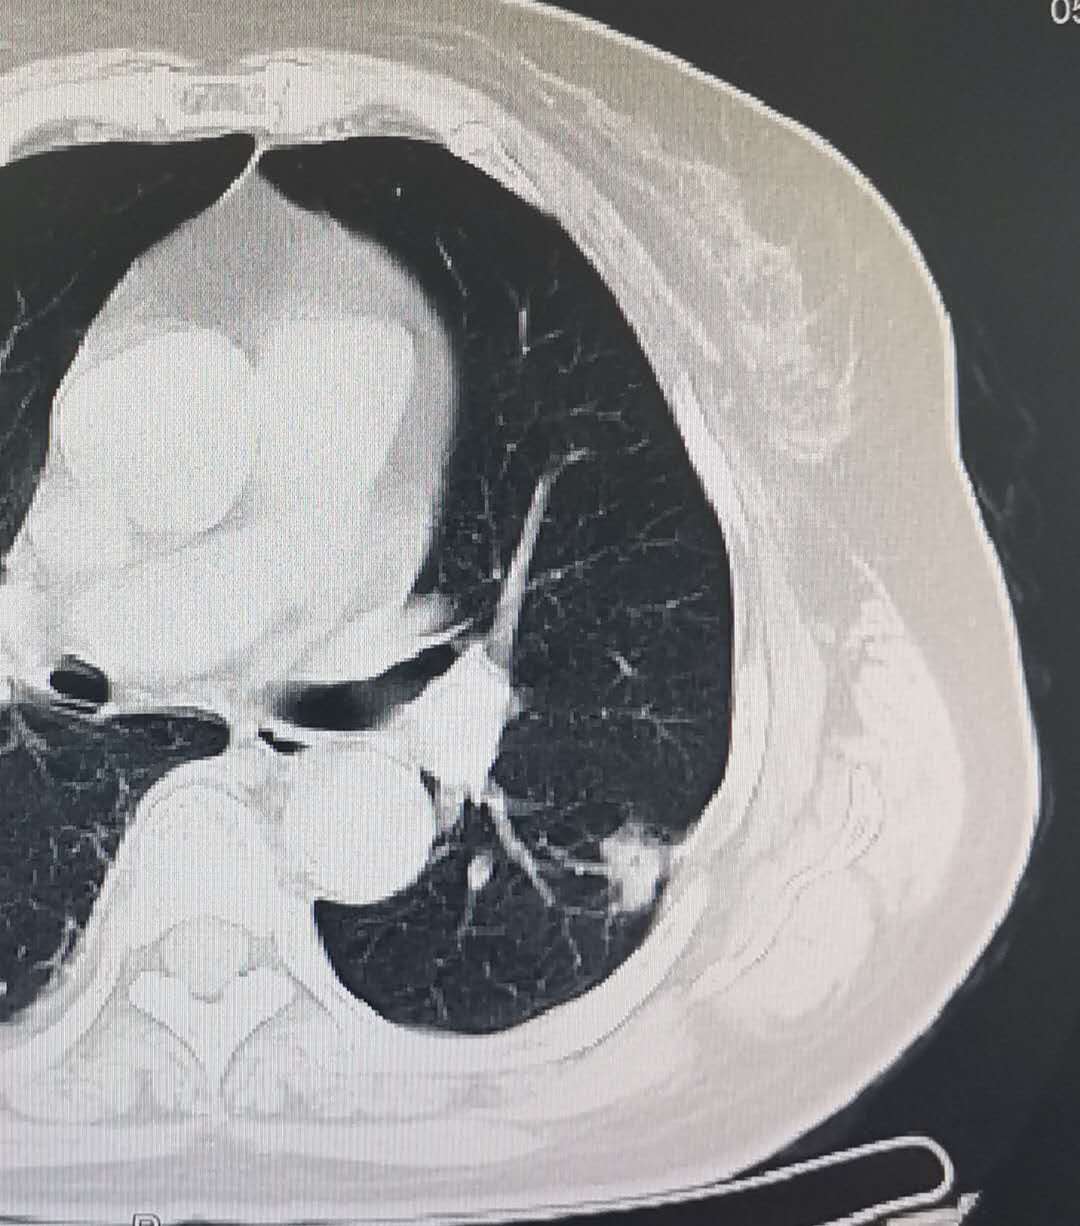

肺癌低剂量螺旋CT筛查是国际公认的金标准!!!

肺癌是我国死亡率最高的恶性肿瘤  。2015年,我国肺癌的发病和死亡例数分别达733,300人和610,200人,发病率和死亡率非常接近,其原因主要是由于临床诊断病例多已为晚期,失去了早期治疗的机会。肺癌预后极差,我国肺癌的5年生存率仅为16.1% 。因此,肺癌的早期诊断和早期治疗是提高肺癌生存、降低肺癌死亡率的重要措施 。  在高危人群中,与X线胸片比较,低剂量螺旋CT可降低60%的肺癌死亡率。

我院在全市率先引进美国GE ACT,具有肺癌低剂量筛查功能和特有的自动筛查成像系统,并唯一取得美国FDA认证。具有扫描速度快、扫描层薄、空间分辨率高、图像质量好、病灶检出率高、对人体辐射剂量小等优点,其辐射剂量相当于普通CT的1/5-1/10。低剂量胸部CT特别适用于单位和个人的健康体检及高危人群普查、肺癌筛查,同时也适用于短期内多次复查及需要长年随诊观察的病人,是一种科学、经济的检查方法,短短几秒,就能让肺结节“无处可逃”,这也是目前世界上筛查早期肺癌最先进的手段。

平原新城医院自开展低剂量CT早期肺癌筛查项目以来,发现多例肺癌早期患者,能让患者在肺癌早期及时得到诊治,提升了肺癌治疗成功率,极大的减轻了患者和家人的负担。